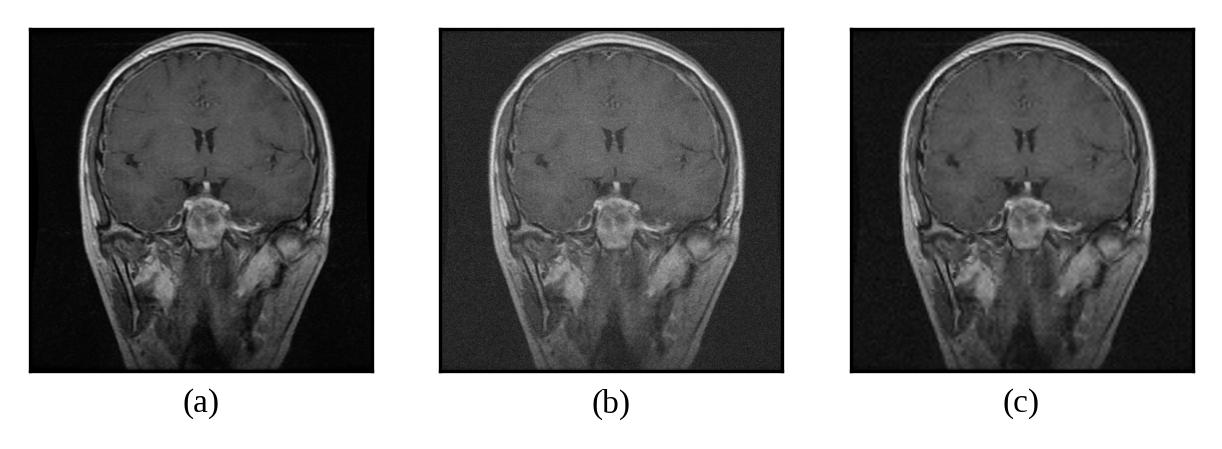

Representative denoising results are illustrated in Figures 2 through 7, demonstrating the visual improvement achieved by both thresholding methods across different noise levels.

Figure 2: (a) Original Image, (b) Noisy Image(μ=0\mu=0, σ=10\sigma=10), (c) Denoised Image (with threshold value τbayes\tau_{bayes})

Refer to caption